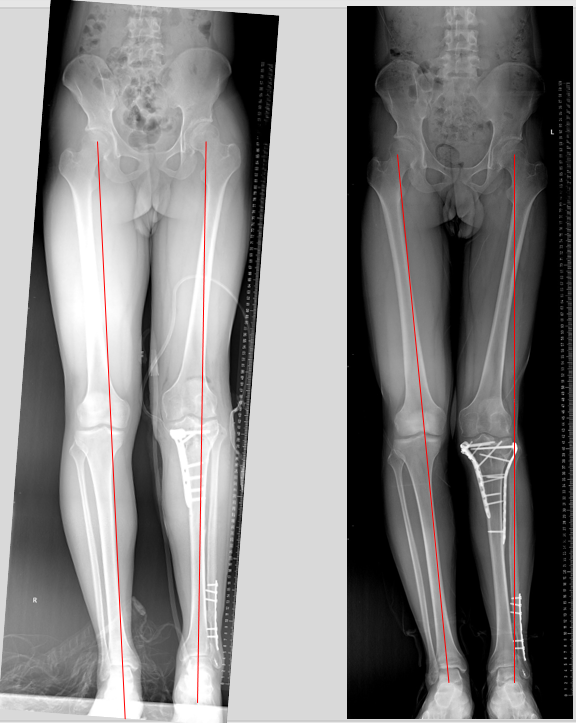

术前显示患肢力线外翻

截骨矫正力线术后后,矫正后(左侧),校正前(右侧)